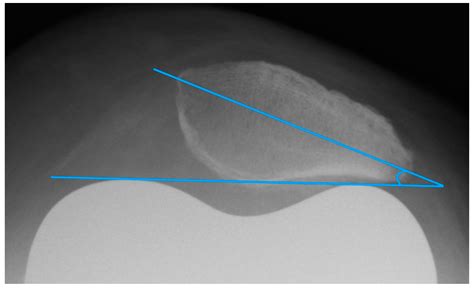

Lateral Patellar Tilt

• lateral patellar tilt angle